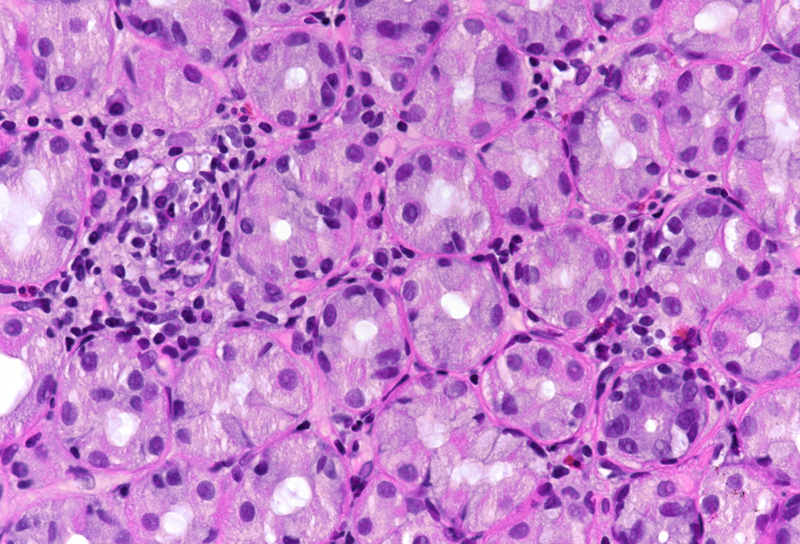

Microscopic examination revealed superficial chronic-active antrum and corpus gastritis (Panel A). In the mucus layer close to the surface epithelium, comma-shaped bacterial structures were detected and highlighted with a Warthin-Starry stain, consistent with Helicobacter pylori (Panel B). In the biopsies obtained from the corpus mucosa, a multifocal, predominantly lymphoplasmacytic infiltrate was seen in deeper parts of the mucosa. Specifically, the oxyntic glands were surrounded and infiltrated by lymphocytes (“emperipolesis”) resulting in gland destruction and parietal cell apoptosis. Occasional eosinophils completed the picture (Panels C-E). No significant atrophy and no metaplastic changes were observed.